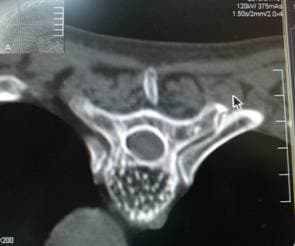

Гемангиома тела позвонка

Структура "пчелиные соты" при гемангиоме